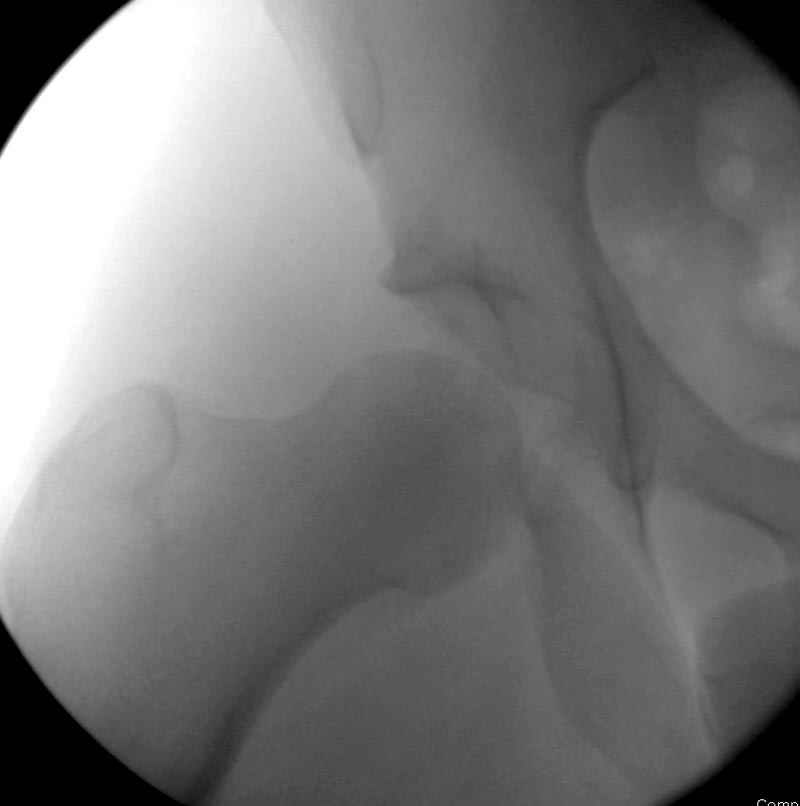

Кроме вывиха виден перелом задней стенки, насчет задней колонны не уверен (видна линия перелома дистальнее ацет. крыши - подвздошная проекция или СТ помогли бы прояснить ситуацию). Поэтому с такой ситуации только закрытое вправление без рефиксации фрагмента задней стенки может привести к рецидиву вывиха (с чем имел неприятность столкнуться не так давно).

На первый взгляд, бедро надо вправить, наложить вытяжение, и дообследовать - Judet views, CT вертлужной впадины, чтобы оценить дефект задней стенки. Вероятно, придется делать остеосинтез заднего края.

5:24 Рентгенограмма таза, вызывают врача ортопеда (снимок N1), его диагноз: закрытый переломо-вывих правого тазабедренного сустава, получает добро на закрытую репозицию в приемном отделении

Интраоперционные N5 косая запирательная и N6 подвздошный снимок